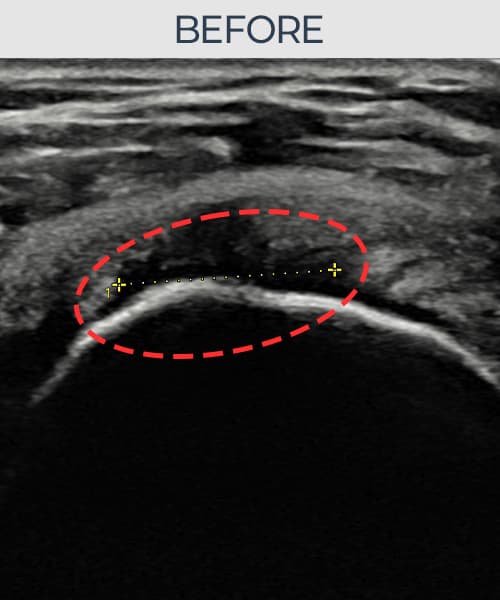

右侧 冈上肌腱 石灰化肌腱炎

13mm × 9mm